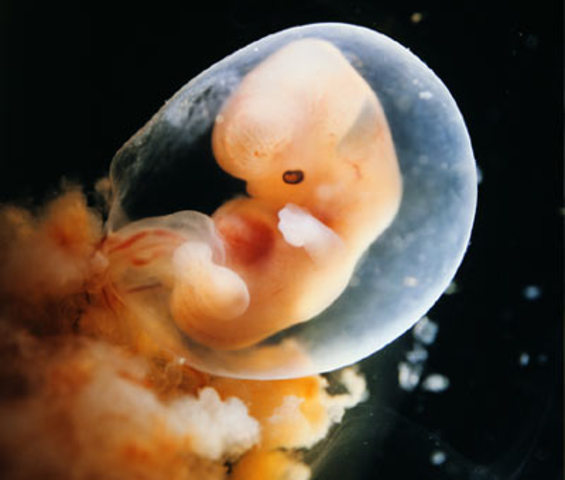

• Organs Begin to Develop

Organs Begin to Develop

Brain, spinal chord, heart, muscles, back bone, ribs, and digestive track start to form at this early stage in the embryonic period.